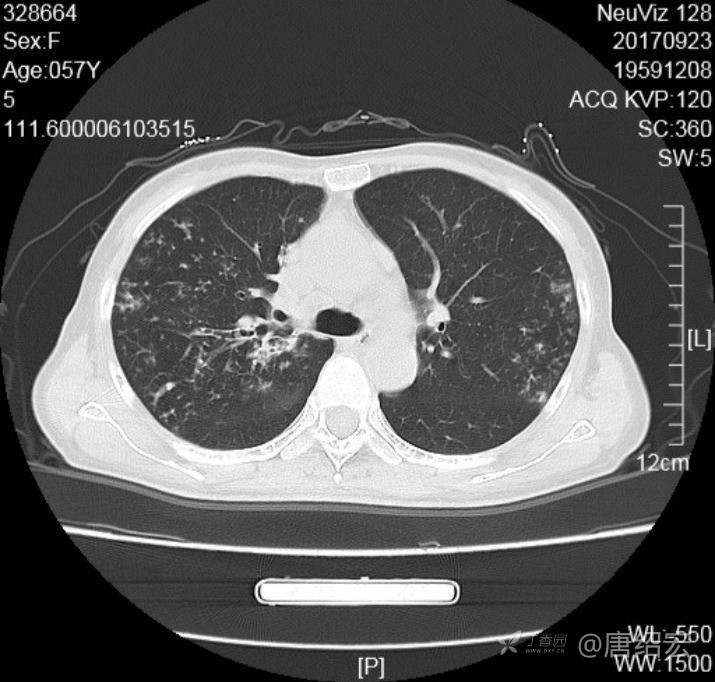

中年女性满肺树芽征还有支气管扩张,考虑什么疾病?

女,57岁,

主诉:发热、咳嗽、咯黄痰,胸闷3天入院。